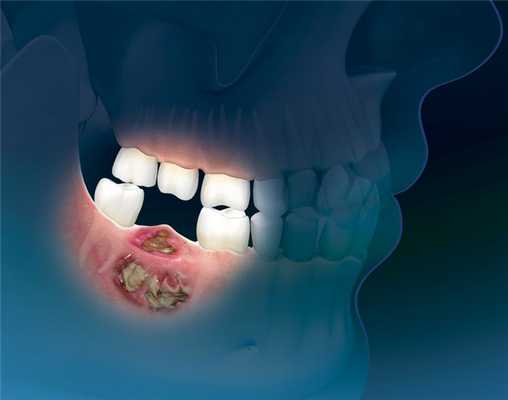

Заболевание развивается, когда опухоль локализуется на слизистой оболочке альвеолярного отростка или мягких тканях дна полости рта c переходом на кость.

Большую роль играет неудовлетворительная гигиена полости рта. Кариозные зубы и плохо изготовленные протезы травмируют слизистую оболочку полости рта, что повышает вероятность развития предрака и рака полости рта.

Часто больные обращаются к врачу, когда опухоль уже достигает больших размеров, отмечается распад новообразования, зловонный запах изо рта, кровотечение. Их также могут беспокоить припухлости или язвы во рту, расшатывание и выпадение зубов, кровоточивость слизистой оболочки полости рта. Позднее присоединяются жалобы на затрудненное открывание рта, трудность или невозможность приема пищи, обилие слюны, похудание.